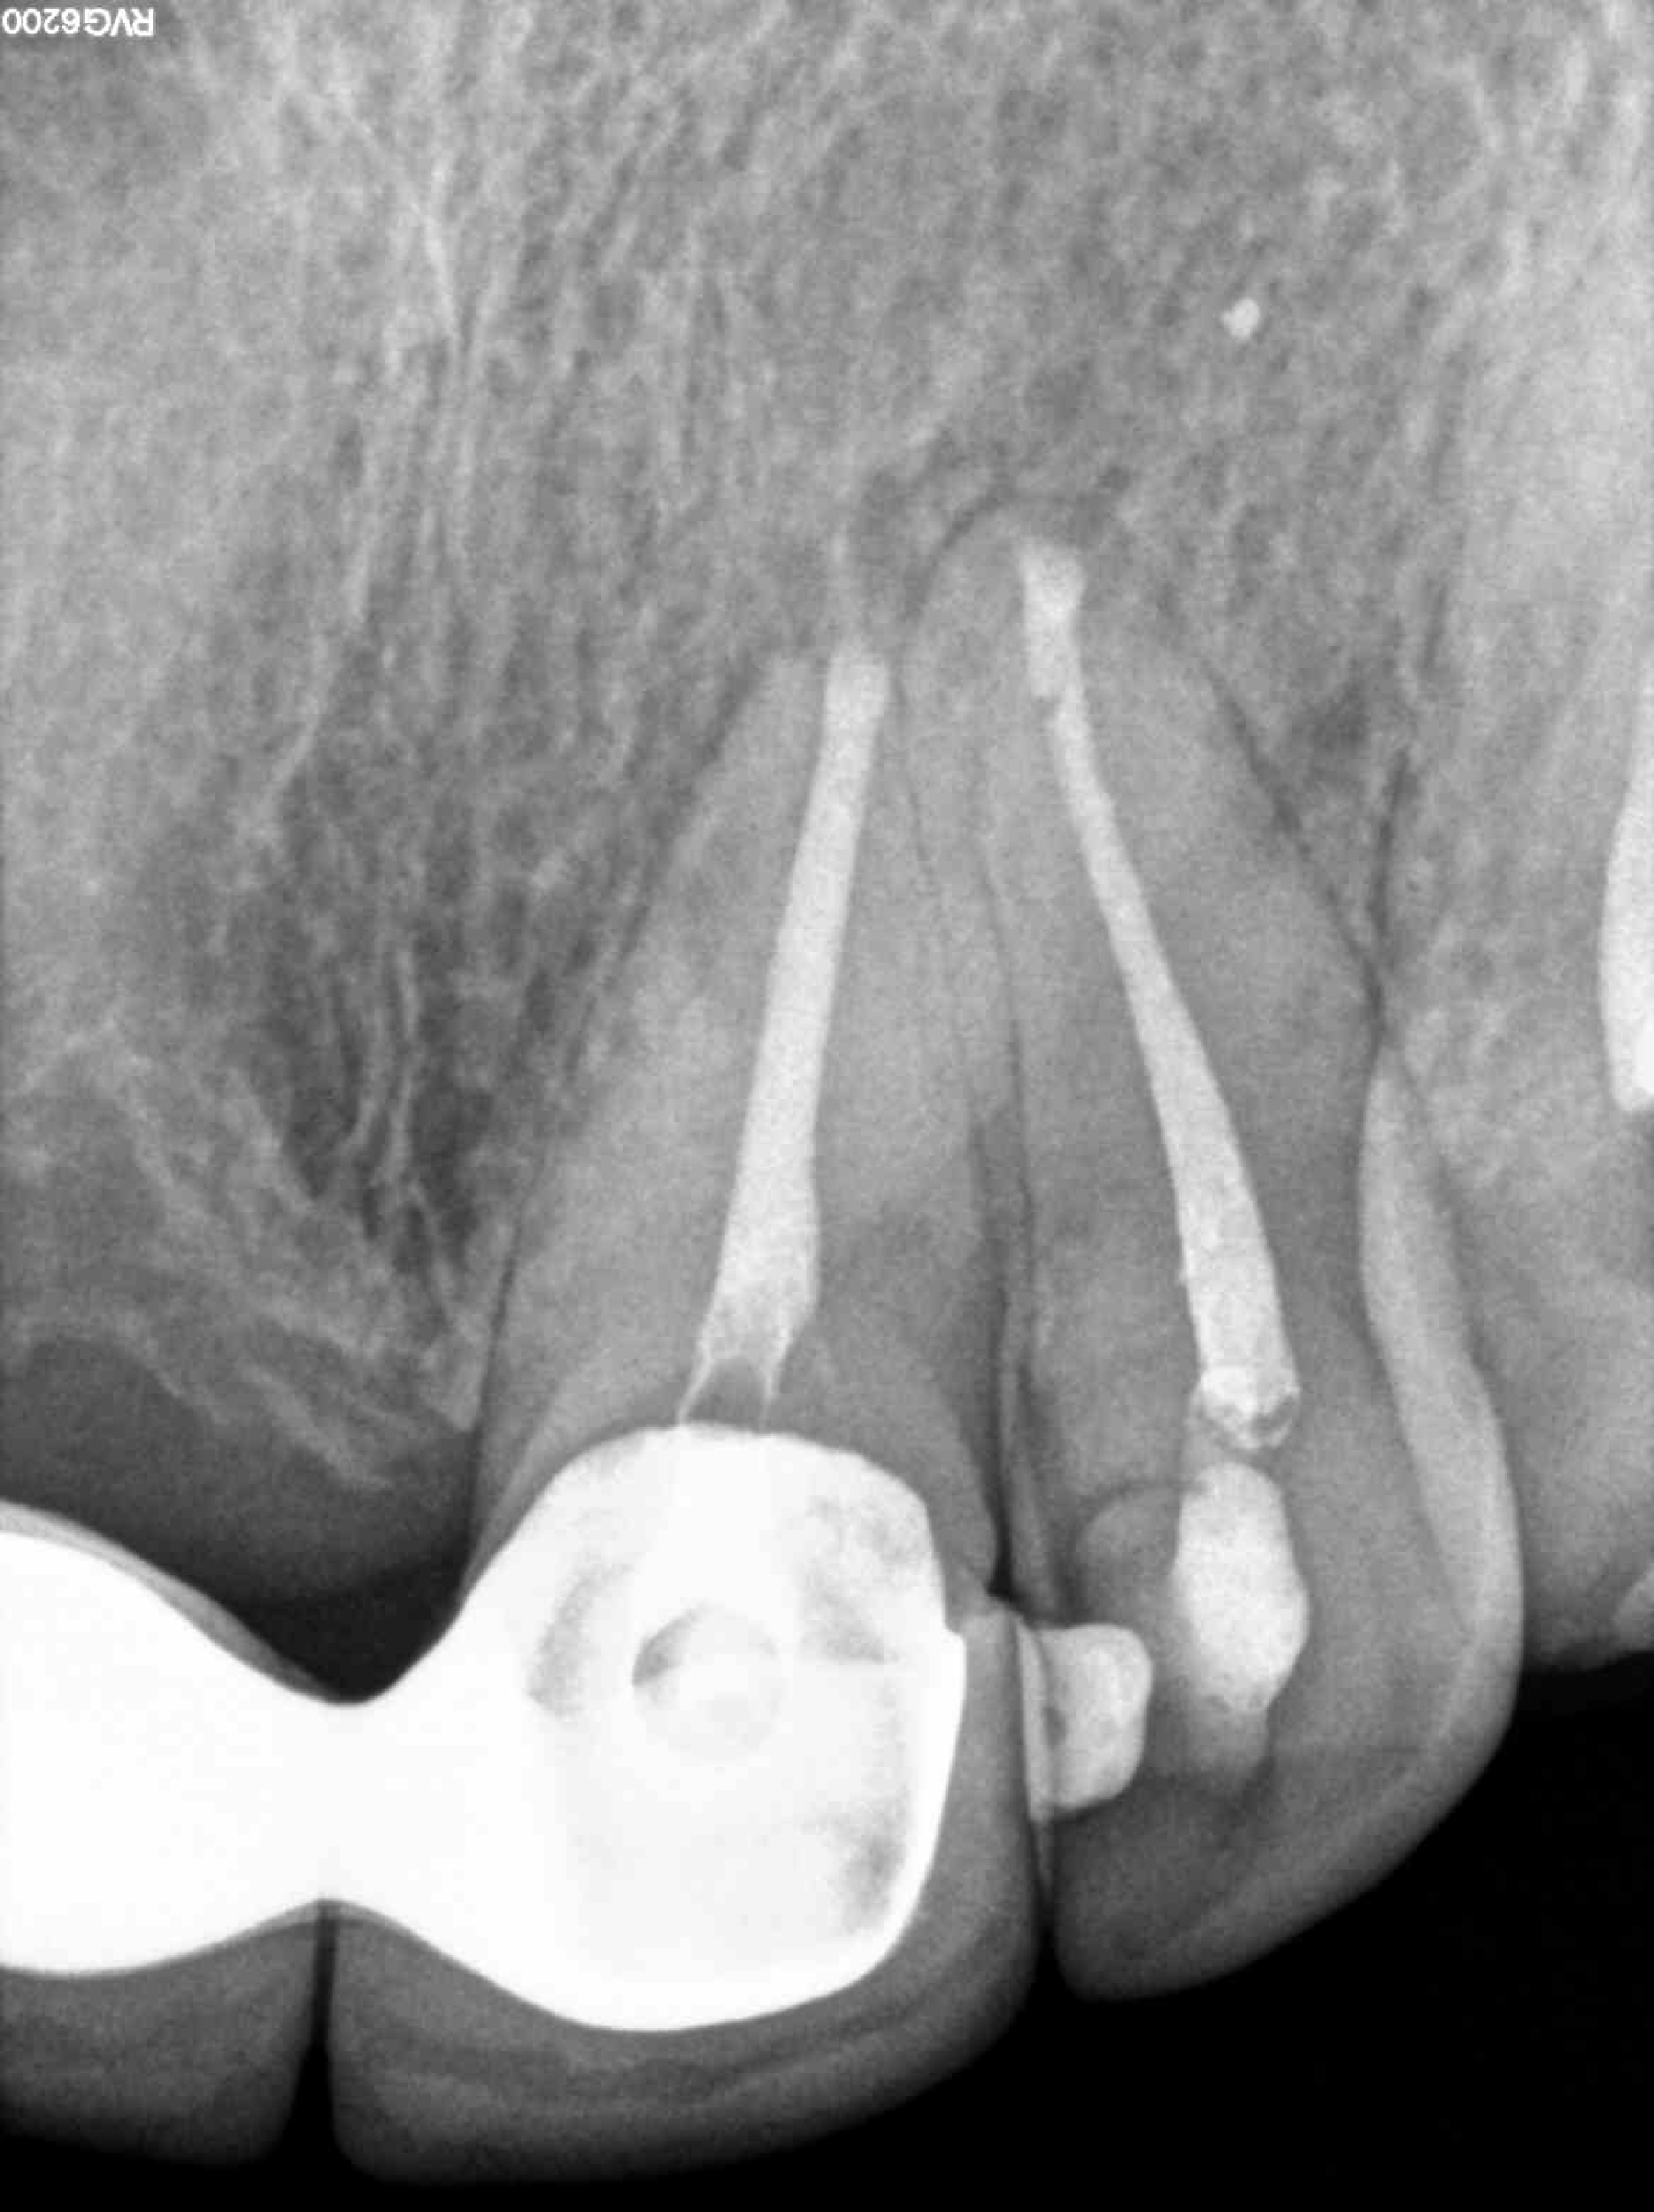

Radiografías

* Haz click sobre las radiografías para verlas a mayor tamaño